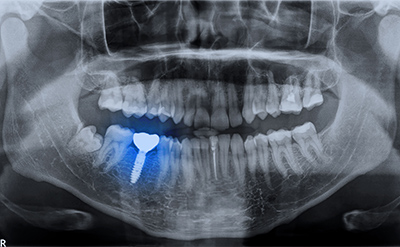

歯科用CT

顎の骨の厚さ・神経・血管の位置を立体的に確認できるため、インプラントを埋める位置や角度を判断しやすくなり、手術中のトラブルを起こりにくくします。